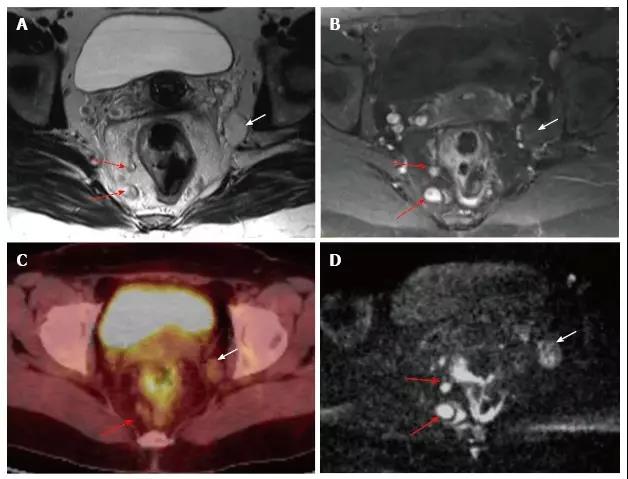

图 16. 直肠系膜和直肠系膜外淋巴结受累。A. T2 加权;B. T1 加权造影增强轴向 MR 图像;C. 18 F-FDG PET-CT;D. DWI 在直肠系膜内(红色箭头)和直肠系膜外(白色区域)显示可疑淋巴结。直肠系膜外淋巴结在 DWI 上比 T2W 和 T1W 序列更为明显。